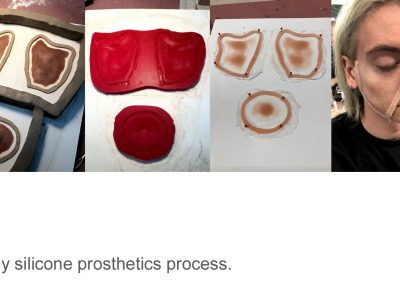

Clinical and Other Media

Candidates with clinical portfolios are expected to provide 10 before and after photographic examples of their clinical work. The most common examples of clinical portfolio work are dental appliances and maxillofacial prosthetics.

Candidates must collect and maintain an Authorization for Release of Health Information form for each patient presented in the Clinical Portfolio – Authorization for Release of Health Information Form PDF. Do Not Submit the Authorization forms with the Clinical Portfolio.

Required Clinical Portfolio Examples:

- Before and after photos, on patient are preferred (Authorization for Release of Health Information Form PDF must be collected but is not submitted)

- Photos of a dental appliance, maxillofacial prosthetic device alone without the patient